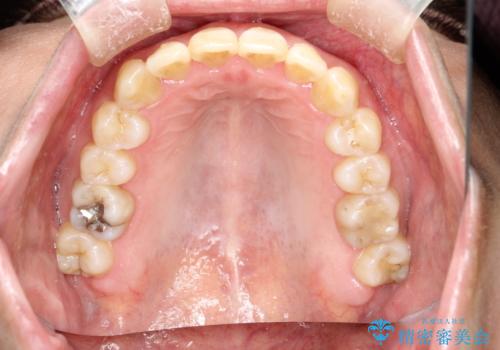

マウスピース枚数 初回52枚 + 追加19枚 + 追加12枚

概ね2年での治療完了となりました。

上の歯列に後方への力をかけるために、患者様には顎間ゴムをマウスピースと共に併用してもらいました。

当院独自の工夫を随所に盛り込み、狙い通りの治療結果が得られました。